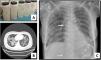

We present a series of three consecutive cases of extracorporeal membrane oxygenation (ECMO) support to perform WLL in patients at risk of complications.Case 1 A 71-year-old woman consulted for worsening dyspnea and supplement oxygen therapy requirement. An interstitial pattern in chest radiography was noted and severe primary PAP diagnosis confirmed by core needle biopsy. Pulmonary function tests showed a restrictive pattern with moderate decrease in diffusion capacity (forced vital capacity [FVC] 1674 mL [72% of predicted value], forced expiratory volume [FEV1] 1575 mL [87%], FEV1/FVC 94%, diffusing capacity of the lung for carbon monoxide [DLCO] 56%, total lung capacity [TLC] 81%). A first WLL was attempted, complicated with progressive respiratory worsening and cardiorespiratory arrest. Procedure was rescheduled after stabilization to be carried out under respiratory support with veno-venous extracorporeal membrane oxygenation (V-V ECMO). After anesthetic induction and intubation with double-lumen endotracheal tube, V-V ECMO was implanted (drainage cannula through left femoral vein [21F] and return cannula through right jugular vein [17F]) (Maquet Cardiopulmonary GmbH, Rastatt, Germany) and maintained with these parameters: flow 3 L/min with FiO2 = 1 and sweep gas of 3 L/min. WLL procedure was completed in a single session by instilling 10 L of saline (1 L aliquots at 37 °C) (Fig. 1A). Ultraprotective ventilation was carried out (volume-limited assist control ventilation with tidal volume 190 mL, respiratory rate 12 bpm, positive end-expiratory pressure [PEEP] 10 cmH2O, FiO2 = 0.9), and no hemodynamic instability occurred. Clinical improvement was observed at 48 h achieving V-V ECMO weaning. Patient was extubated at 72 h and discharged 9 days later, with oxygen discontinuation and radiological improvement. A. Characteristic fluid extracted during WLL, initially with a milky appearance and progressive clearing. B. High-resolution chest CT. Lung parenchyma with extensive ground-glass opacities and associated septal thickening (typical “crazy paving” pattern). C. Chest radiograph. Extensive bilateral alveolointerstitial infiltrates; ECMO cannulae (arrows) properly positioned, with separation >10 cm to minimize recirculation phenomenon. A 35-year-old woman, former smoker, was admitted for progressive dyspnea and respiratory failure. High-resolution chest computed tomography (CT) found extensive “crazy paving” foci suggestive of PAP (Fig. 1B); bronchoalveolar lavage and transbronchial biopsy confirmed the diagnosis. Respiratory function tests showed a normal spirometric pattern with moderately decreased diffusion (FVC 2890 mL [90%], FEV1 2650 mL [98%], FEV1/FVC 92%, DLCO 54%). WLL procedure was scheduled under V-V ECMO. Introducer sheaths were placed in both femoral veins under local anesthesia and sedation, prior to anesthetic induction; after that ECMO was implanted (23F left femoral drainage cannula, 17F right femoral tip-perforated 50-cm return cannula). Extracorporeal support (flow 3 L/min with FiO2 = 1 and sweep gas 2 L/min) and protective one-lung ventilation (volume-limited assist control ventilation with tidal volume 150 mL, respiratory rate 15 bpm, PEEP 8 cmH2O, FiO2 = 0.5) via double-lumen tube were started, performing bilateral lung lavage with saline at 37 °C, through 10 aliquots of 900 mL in each lung. ECMO weaning was attained 12 h later and extubation 48 h after the procedure. ICU stay was 3 days, being discharged home 10 days after the WLL without the need for home oxygen therapy. A 51-year-old woman with previous diagnosis of PAP required ICU admission with respiratory failure. Respiratory function tests presented mild restrictive pattern and severe diffusion impairment (FVC 1570 mL [62%], FEV1 1539 mL [71%], FEV1/FVC 97%, DLCO 28%, TLC 76%). Anesthetic induction with double-lumen tube intubation was performed, prior to implantation of ECMO cannulae (21F drainage cannula through left femoral vein and 50 cm tip-perforated 17 F return cannula through right femoral vein) (Fig. 1C). ECMO parameters were flow 2.6 L/min with FiO2 = 1 and sweep gas 2 L/min. Ultra-protective mechanical ventilation parameters were established (pressure-limited assist control ventilation, maintaining a driving pressure of 10 cmH2O and initial PEEP of 5 cmH2O), and WLL was performed with 10 aliquots of 800 mL in each lung. The procedure was uneventful, achieving ECMO support weaning and extubation 48 h after the procedure. The ICU stay was 5 days, and she was discharged home 8 days after the WLL, without chronic oxygen therapy requirements.